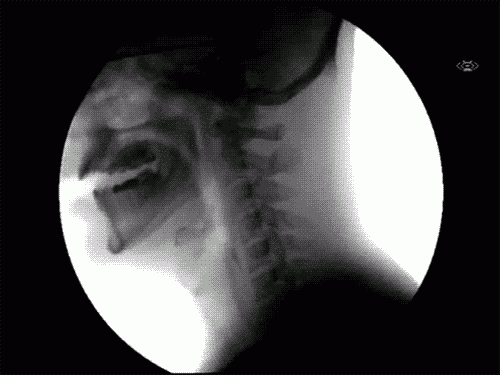

6.當我們吞東西時的身體運作模式。